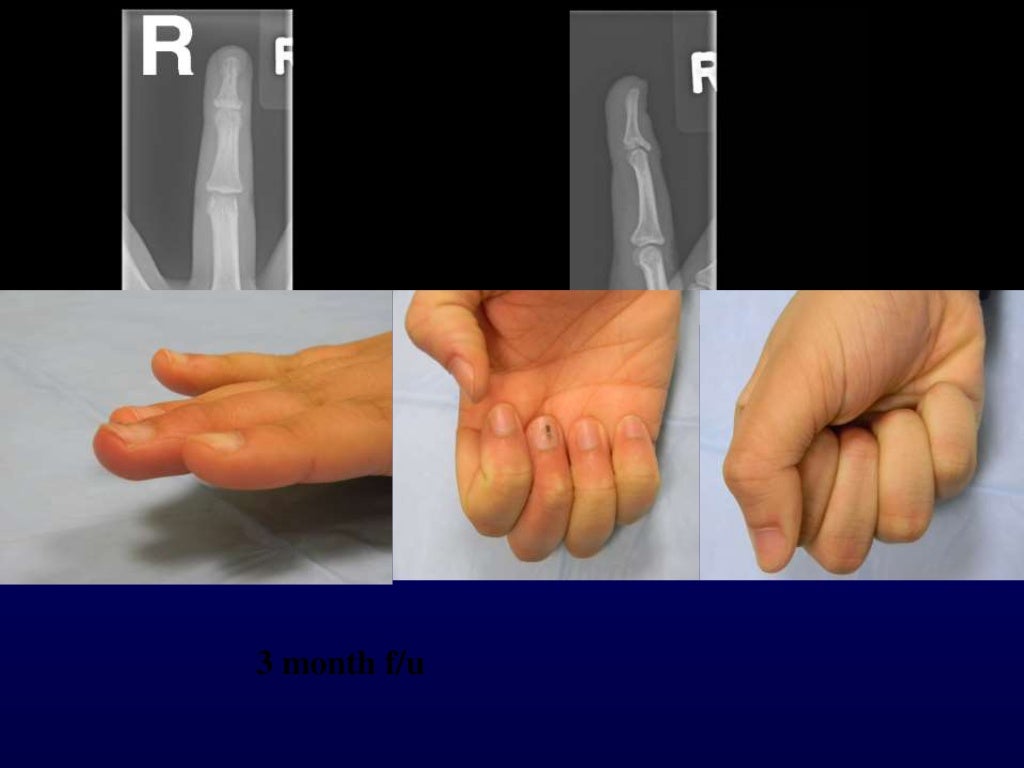

Trauma Percutaneous Pin Stabilization with Thermoplastic Bonding

Percutaneous pin fixation of the mallet fracture, review of the techn… Percutaneous Pin Fixation percutaneous fixation of proximal humeral fractures involves careful patient selection and appropriate timing of. percutaneous pinning by kirschner wire intramedullary fixation, which is less invasive, is the first choice for the surgical. percutaneous pin placement options include retrograde lateral, retrograde anterior, retrograde anterolateral,. Protect skin from pins with felt,. with unstable scfes, before manipulation of the. Percutaneous Pin Fixation.

Trauma Percutaneous fixation of proximal fracture of the proximal phalanx Percutaneous Pin Fixation percutaneous pin placement options include retrograde lateral, retrograde anterior, retrograde anterolateral,. percutaneous fixation of proximal humeral fractures involves careful patient selection and appropriate timing of. percutaneous pinning by kirschner wire intramedullary fixation, which is less invasive, is the first choice for the surgical. with unstable scfes, before manipulation of the leg for lateral views, consider initial. Percutaneous Pin Fixation.